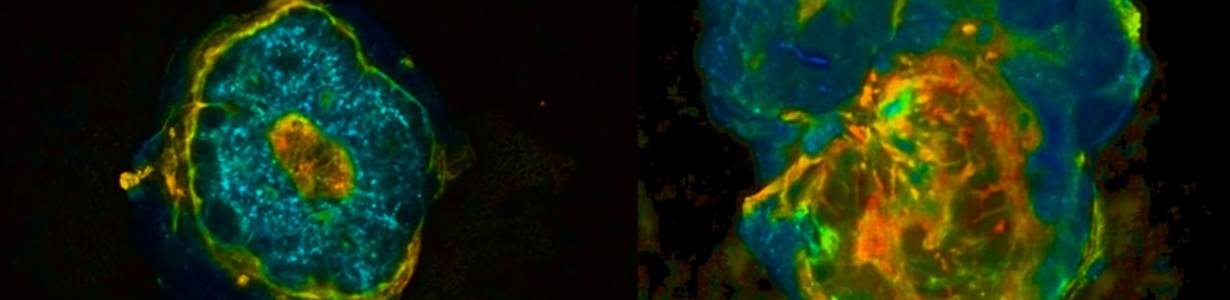

Суть метода в оптической экспресс-биопсии с использованием флуоресцентного макроимиджинга с временным разрешением. Эффективность технологии уже подтверждена на образцах 47 пациенток Нижегородского онкодиспансера с раком молочной железы.

Фото: t.me/pimunn